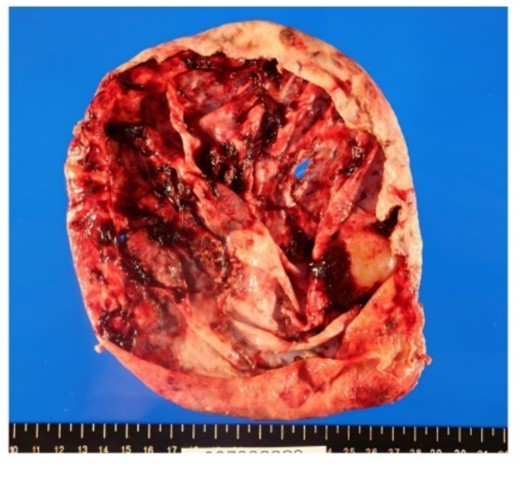

Surgical specimen showed no neoplastic lesion (Fig. 5). Pathological diagnosis was a non-parasitic simple hepatic cyst with acute inflammation and hemorrhage. The cystic wall presented bile duct epithelium and liver lobules. Immunohistochemical staining showed that only CA19-9 was positive in the hepatic cyst wall epithelium (Fig. 6). The patient’s serum levels of CA19-9, CA125 and CEA were 164.0 U/mL, 126.3 U/mL, and 1.0 ng/mL, respectively, on postoperative day 23. A follow-up abdominal CT scan performed 2 months after the surgery did not show any sign of tumor.